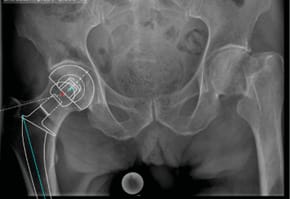

Case 1: Instability after primary cementless total hip arthroplasty (32-year-old female)

A female patient with recurrent dislocations following a cementless primary total hip arthroplasty (THA) was treated using head exchange with BioBall® 2XL standard adapter. The offset correction improved soft tissue tension and joint stability. No further dislocations were observed during a 10-year follow-up.